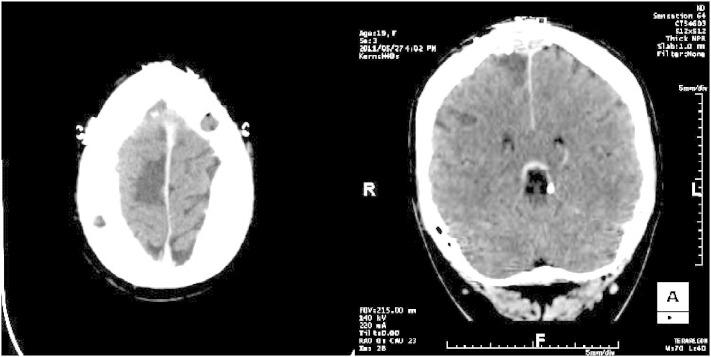

Identifying the epileptogenic zone (EZ) in patients with refractory nonlesional frontal lobe epilepsy is frequently challenging. Intracranial EEG (icEEG) recordings are often required to better delineate the EZ, but the presence of an extensive network of connections allowing rapid ictal spread may result in bilateral homologous regional (or extremely diffuse) electrical ictal patterns. Here, we report a case where callosotomy performed after a first nonlateralizing icEEG study allowed for adequate identification of the EZ. The patient, an 18-year-old left-handed woman with daily atonic spells, had synchronous interictal and ictal epileptic activity from both supplementary motor areas (SMAs) during icEEG. Anterior partial callosotomy localized the EZ to the right SMA, as seizures were no longer associated with mirror-image ictal activity over the left SMA. Right SMA resection led to seizure freedom (follow-up of 23 months). This case exemplifies how a partial callosotomy followed by further icEEG recordings may adequately localize the EZ when initial icEEG recordings reveal bilateral synchronous focal or regional ictal activities.

在难治性非病变额叶癫痫患者中识别致痫区(EZ)通常具有挑战性。通常需要进行颅内脑电图(icEEG)记录以更好地描绘致痫区,但广泛的连接网络允许癫痫快速传播,这可能导致双侧同源区域(或极其弥漫)的癫痫发作期电活动模式。在此,我们报告一例病例,在首次非定位性icEEG研究后进行胼胝体切开术,从而能够充分识别致痫区。该患者为一名18岁的左利手女性,每天发作失张力发作,在icEEG期间双侧辅助运动区(SMA)存在发作间期和发作期同步癫痫活动。前部胼胝体切开术将致痫区定位至右侧SMA,因为癫痫发作不再与左侧SMA的镜像发作期活动相关。右侧SMA切除术使患者不再发作(随访23个月)。该病例表明,当初始icEEG记录显示双侧同步局灶性或区域性发作期活动时,先行部分胼胝体切开术,随后进一步进行icEEG记录,可能会充分定位致痫区。